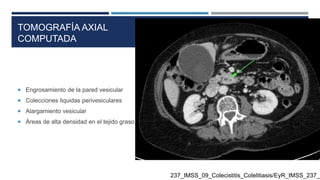

TOMOGRAFÍA AXIAL

COMPUTADA

 Engrosamiento de la pared vesicular

 Colecciones liquidas perivesiculares

 Alargamiento vesicular

 Àreas de alta densidad en el tejido graso perivesicular

TOMOGRAFÍA AXIAL COMPUTADA  Engrosamientode la pared vesicular  Colecciones liquidas perivesiculares  Alargamiento vesicular  Àreas de alta densidad en el tejido graso perivesicular 237_IMSS_09_Colecistitis_Colelitiasis/EyR_IMSS_237_0